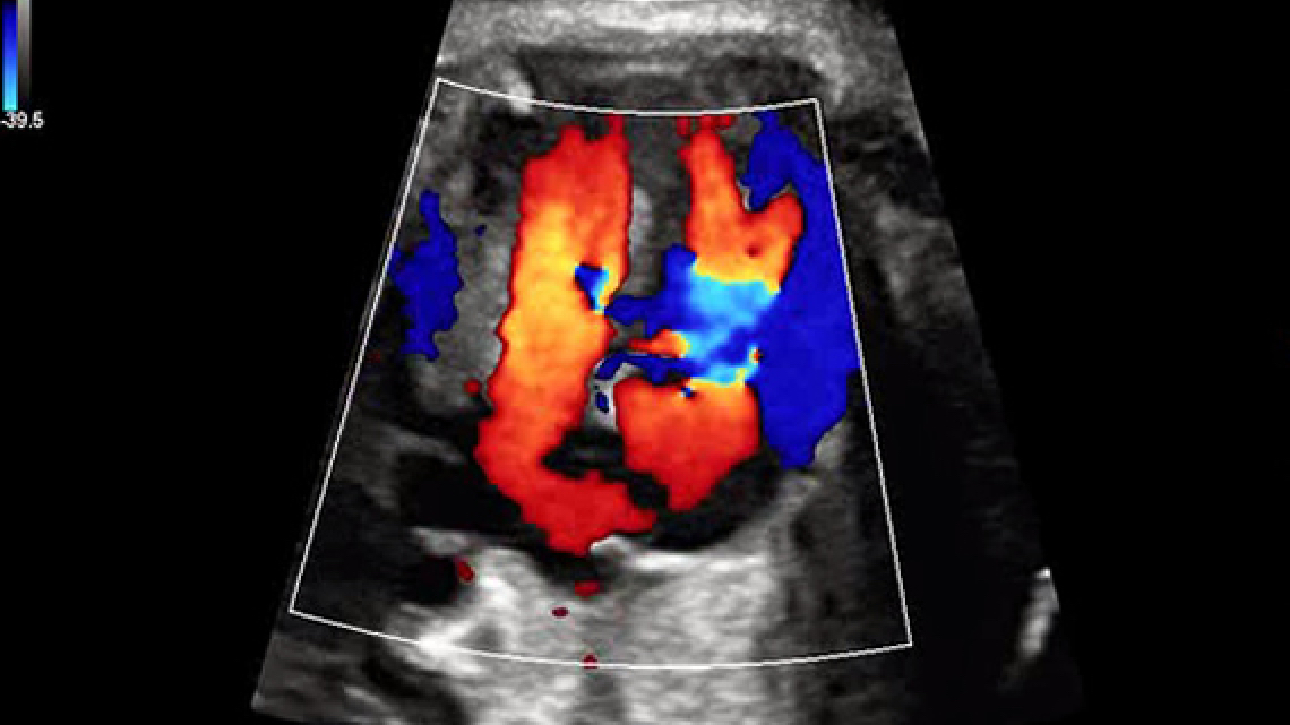

ImĂĄgenes clĂnicas